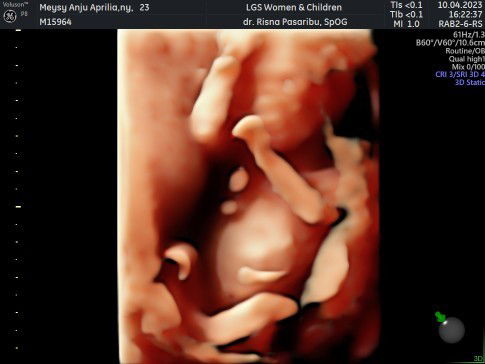

Alhamdulillah sudah lahir anak kedua ku. HPL 20 September, lahir 19 September dengan proses Cesar. Jenis kelamin bayi Laki-laki Lahir dengan berat 3.8kg Panjang Lahir 49cm Niatnya mau lahiran normal, tapi adek bayi kenceng terus ga mules mules, sudah keluar flek pun gamules sama sekali. Jadi tgl 18 saya USG ke dokter, dan langsung di kasih jadwal Cesar karena ternyata bayiku besar gak masuk panggul dan ketuban sudah lengket. Sempet deg degan tapi pas bayi sudah lahir sehat sudah sedikit lega. Tinggal proses recovery yang panjang karena ternyata lebih enak lahiran normal menurut ku (anak pertamaku lahir normal/pervaginam)🙂🙂#firstbaby